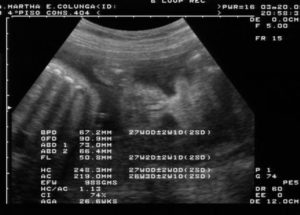

На 15-й неделе врач-сонолог оценивает следующие показатели:

- Длина плода;

- Степень развития носовых костей;

- Ширина воротникового пространства;

- Длина бедра;

- Бипариетальный размер головы;

- Плацента (толщина, высота);

- Частота сокращений сердца;

- Состояние внутренних органов.